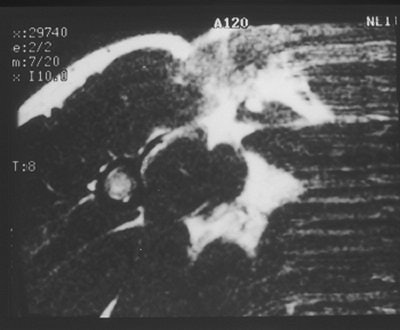

| An axial fast SE T2-weighted image [TR/effective TE (ms) 3100/91.3] shows disruption of the pectoralis major muscle near its attachment to the humerus. The linear low signal structure extending medially from the humerus was confirmed at surgery to represent torn residual tendon. |